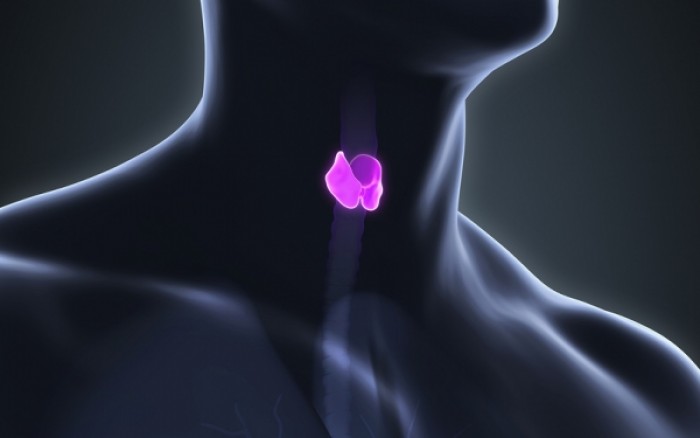

Ο θυρεοειδής, ο μικρός αδένας σε σχήμα πεταλούδας που βρίσκεται στο λάρυγγα, επηρεάζει πολυάριθμες λειτουργίες του σώματος.